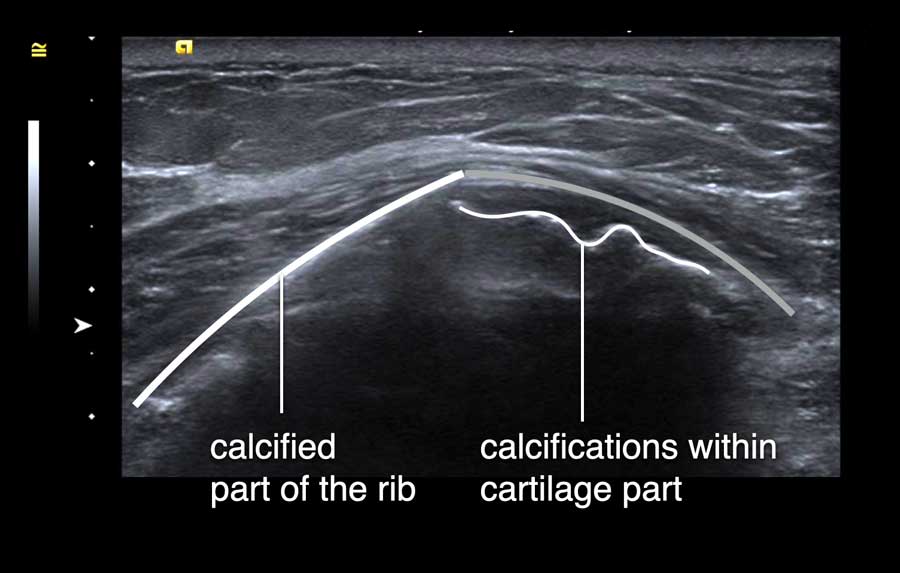

Một xương sườn nhô ra có thể tạo thành một khối cứng lồi lên, dễ nhầm lẫn với khối u vú.

Bệnh nhân này than phiền về một khối cứng đau trong vú.

Trên siêu âm, ghi nhận hình ảnh khớp sụn-xương sườn nhô ra.

Đây là vị trí tiếp nối giữa phần xương đã vôi hóa của xương sườn và phần sụn.

Các vôi hóa thường có thể được quan sát thấy trong phần sụn, như trong trường hợp này.

Video này minh họa hình ảnh sụn xương sườn bình thường.

Bằng cách xoay đầu dò, có thể thấy xương sườn là một cấu trúc chạy dọc, nằm phía trước phổi và phía sau cơ ngực.